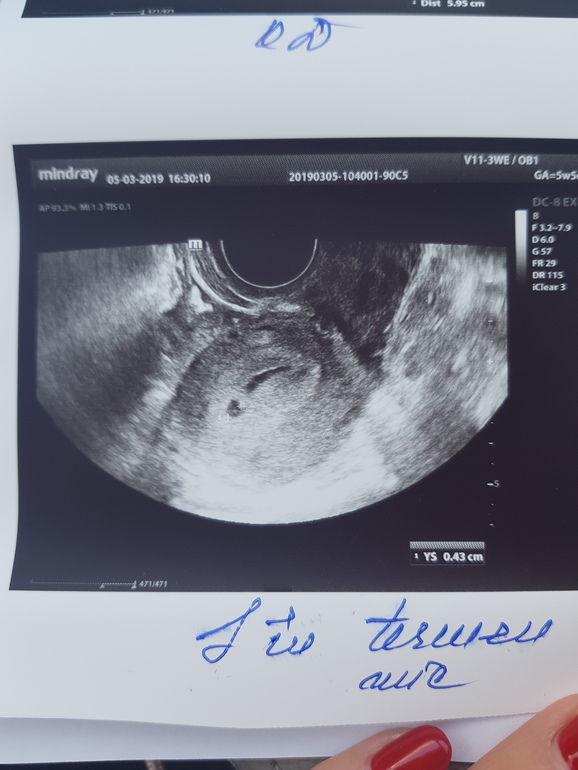

По месячным 5нед6дней, но овуляция была на неделю позже и срок меньше. Вчера была на узи, чтобы исключить внематочную. Нашли плодное яйцо 4,3 мм и большую гематому рядом 19,1 на 5,6 мм. И еще кисту желтого тела 5 см. Узист напугала страшно. Угроза выкидыша, полный покой, никаких каблуков и секса. Я отправила узи врачу, сказал подходить в четверг, до четверга ничего не предпринимать.

Вот фото узи

Гематома